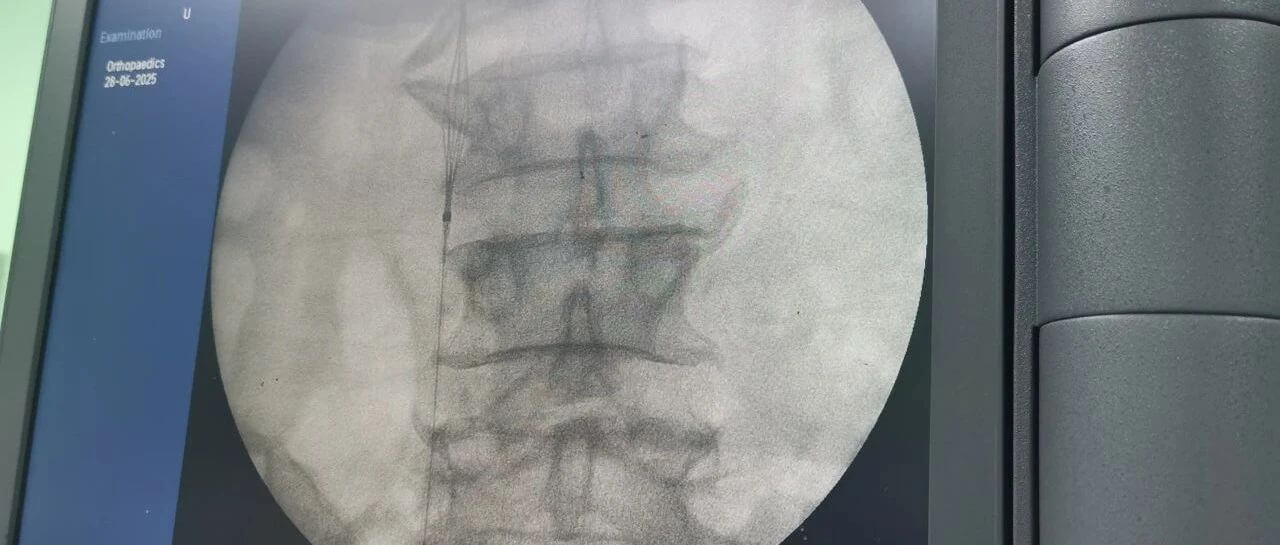

面對(duì)這一嚴(yán)峻挑戰(zhàn),羅軍副院長(zhǎng)團(tuán)隊(duì)果斷決策,先行實(shí)施“下腔靜脈濾器植入術(shù)”。手術(shù)團(tuán)隊(duì)?wèi){借精湛的技術(shù),在患者的下腔靜脈(人體最大的靜脈干)內(nèi)精準(zhǔn)放置了一個(gè)特殊的“濾網(wǎng)”裝置——腔靜脈濾器。它的核心作用就是充當(dāng)“血栓攔截網(wǎng)”:

攔截脫落的血栓:有效捕捉從下肢深靜脈脫落的血栓碎片,防止其隨血流進(jìn)入心臟和肺部。

預(yù)防致命肺栓塞:從根本上大幅降低患者在骨折手術(shù)期間及術(shù)后康復(fù)階段發(fā)生肺栓塞的風(fēng)險(xiǎn)。

保障后續(xù)手術(shù)安全:為接下來(lái)必須進(jìn)行的、耗時(shí)較長(zhǎng)的骨盆髖臼粉碎性骨折修復(fù)手術(shù)(尤其是利用3D打印技術(shù)進(jìn)行的精準(zhǔn)手術(shù))掃除了最大的安全隱患,提供了至關(guān)重要的手術(shù)安全保障期。